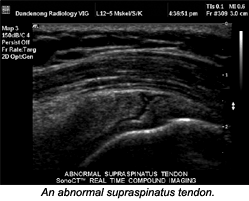

On sonograms, the distinctive signs of tendonitis are hypoechoic foci, with or without tendon thickening. With high-resolution imaging, the lesions appear oval with blurred borders, and seem to be orientated parallel to the course of the tendon fibers. In later stages, generalized thickening with widening of the distance between fascicles is present. Abnormalities of the tendon sheath are, in most cases, clearly visible in the form of hypoechoic thickening of the sheath, due to fluid accumulation.

Signs of fresh tendon rupture are similarly visible with sonography or MR, at least in principle. When using ultrasound, characteristic findings, such as thinning or disruption of fibers, may be masked by an overlying hypoechoic hematoma or artifacts. With sonography, partial tears principally are visible in the form of circumscribed hypoechoic lesions. Ultrasound and MR may be used jointly to diagnose tendon diseases, and for clinical follow-up.